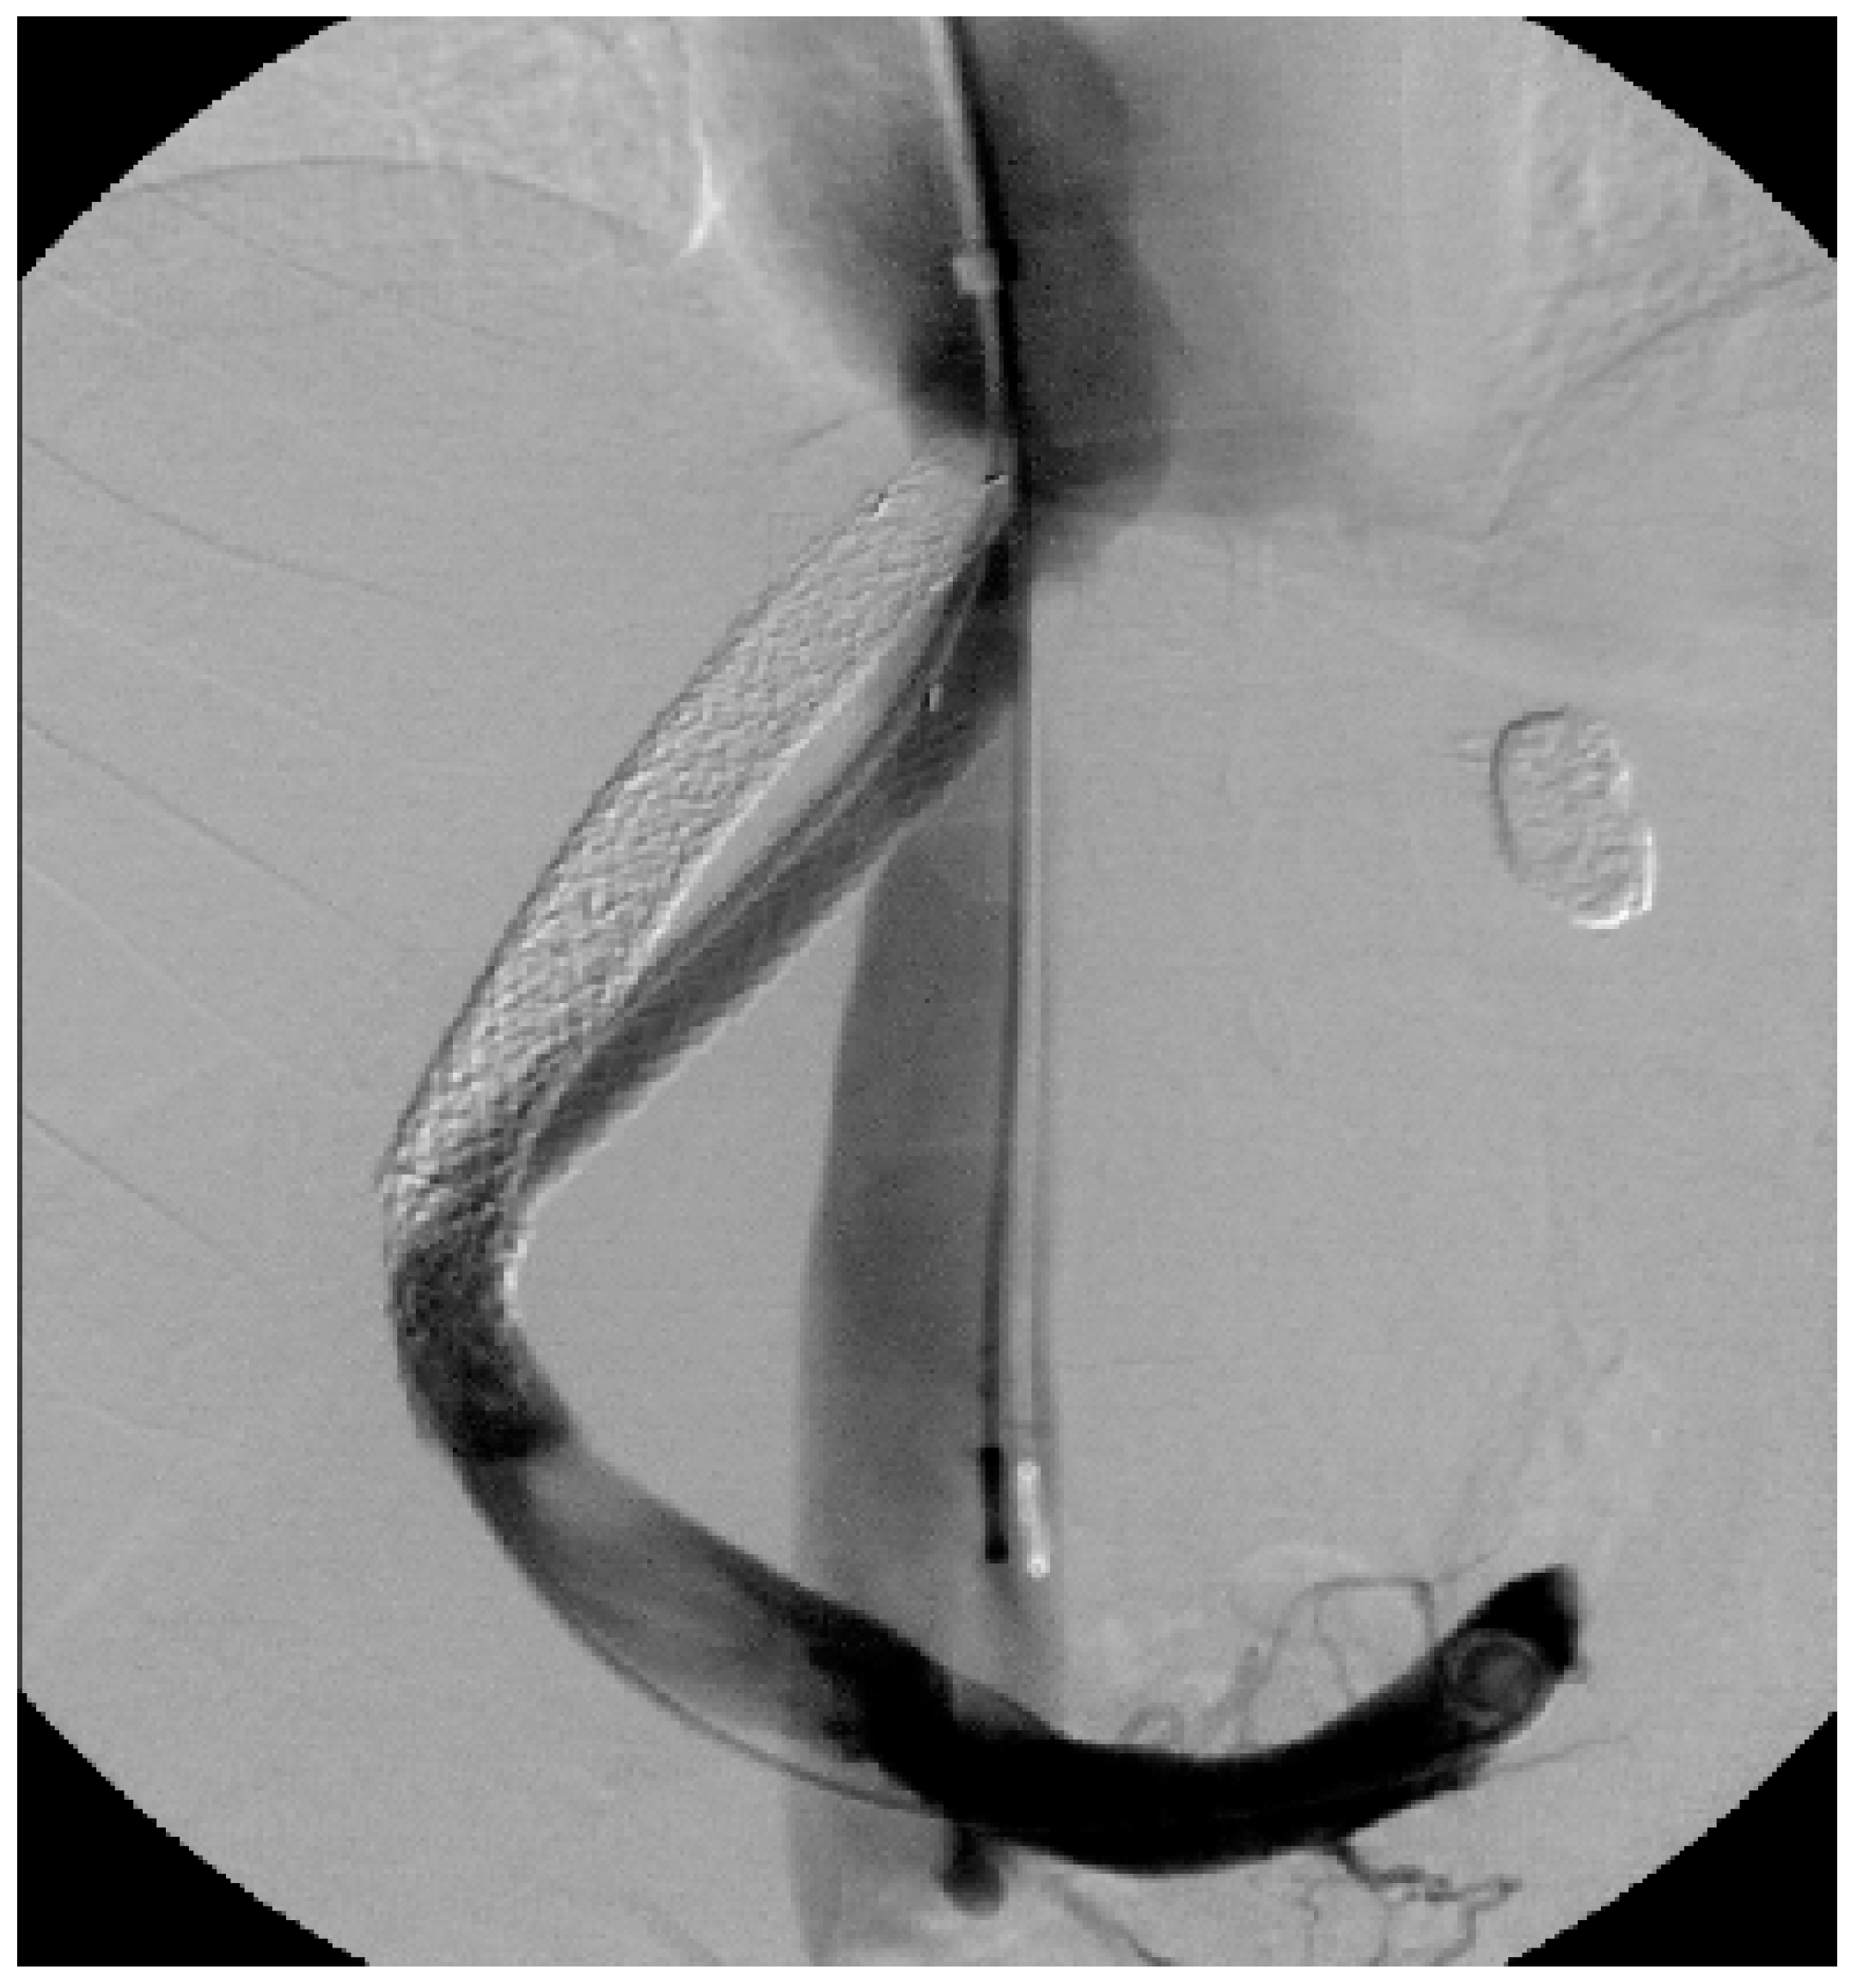

2.2. TIPS

2.2.2. Technique of TIPS Implantation